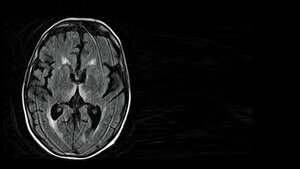

Premium Kardiologie 02.01.18 Jacqueline FluxMyokarditisApparative Diagnostik durch die MTA Unter einer Myokarditis versteht man die Schädigung der Herzmuskelzellen durch deren Infiltration…